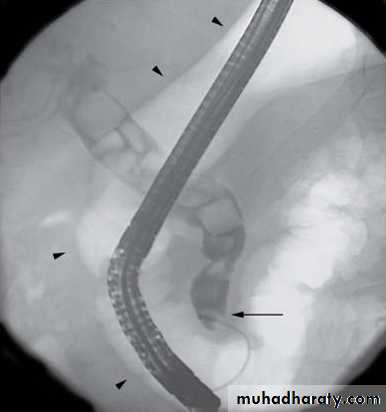

Endoscopic retrograde cholangiopanreatography (ERCP)

Side veiwing endoscopieCannulation of ampulla of Vater

Injection of contrast to visualize the bile ducts

Also bile can be taken for cytological and microbiological tests

Brushings from strictures to decide whether benign or malignant